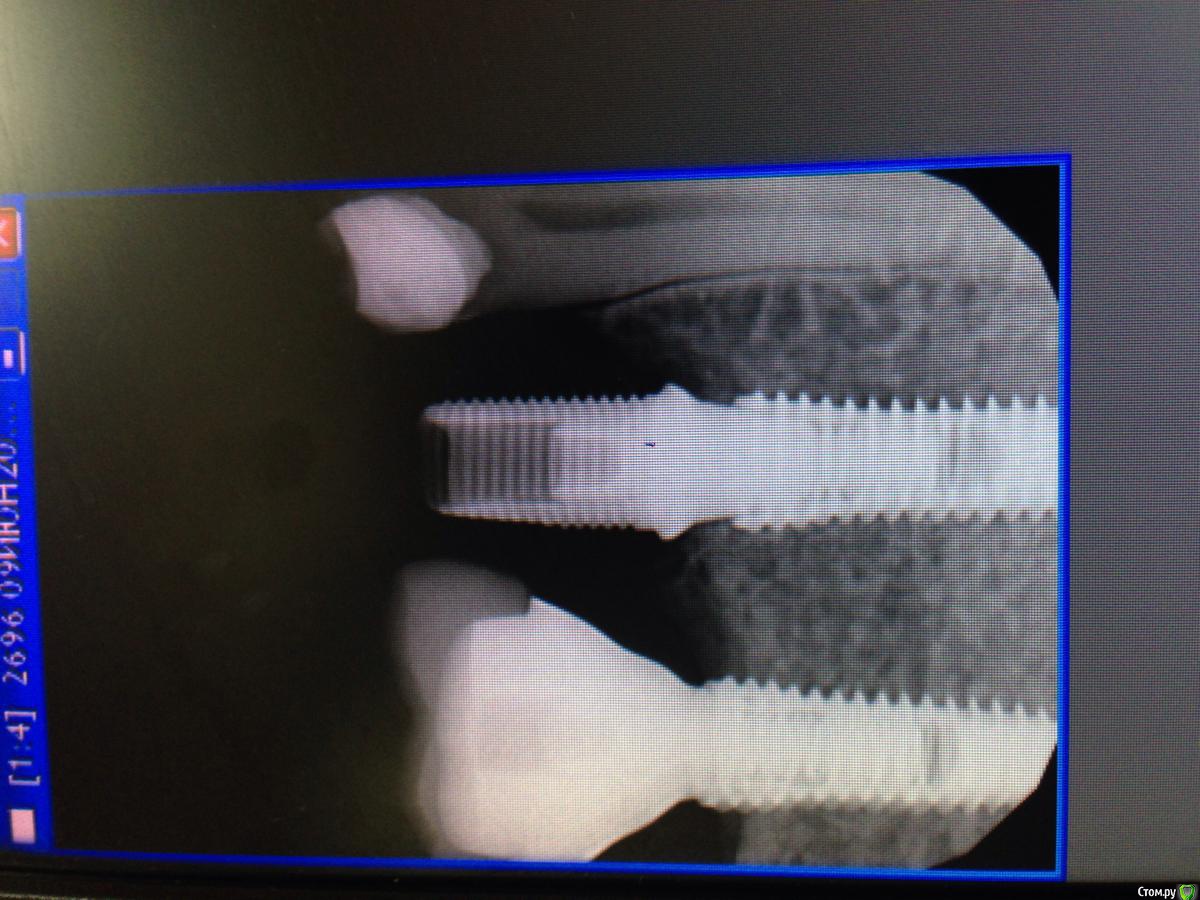

Magomed Опубликовано 22 июня, 2016 Поделиться Опубликовано 22 июня, 2016 снимок бы посмотреть. Ссылка на комментарий

Magomed Опубликовано 22 июня, 2016 Поделиться Опубликовано 22 июня, 2016 просто хочется посмотреть,после заглубления что с костью Ссылка на комментарий

Acidrocker Опубликовано 23 июня, 2016 Автор Поделиться Опубликовано 23 июня, 2016 (изменено) просто хочется посмотреть,после заглубления что с костью P.S. Почему-то боком загрузилось. Изменено 23 июня, 2016 пользователем Acidrocker 3 Ссылка на комментарий